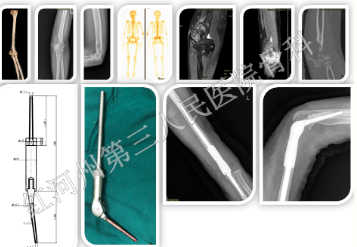

例如一位50岁女性患者,经过穿刺确诊为桡骨远端软骨肉瘤,术前疼痛评分8分。处理:术前通过MRI确认截骨平面。通过CT三维重建获取数据,定制桡骨远端假体,行保肢手术:桡骨瘤段切除定制假体重建术,术后腕关节功能恢复理想,疼痛迅速下降为1分。

另外一位50岁女性病患者,左侧肱骨远端溶骨病变,经过取材活检,诊断棕色瘤,因肱骨远端累及关节面且关节周围大部分骨组织破坏,无生物重建(植骨促进愈合)条件,经过MRI确定截骨平面,经过CT三维重建定制肘关节假体,行肱骨远端瘤段切除定制肘关节假体重建,术后快速恢复肘关节功能。